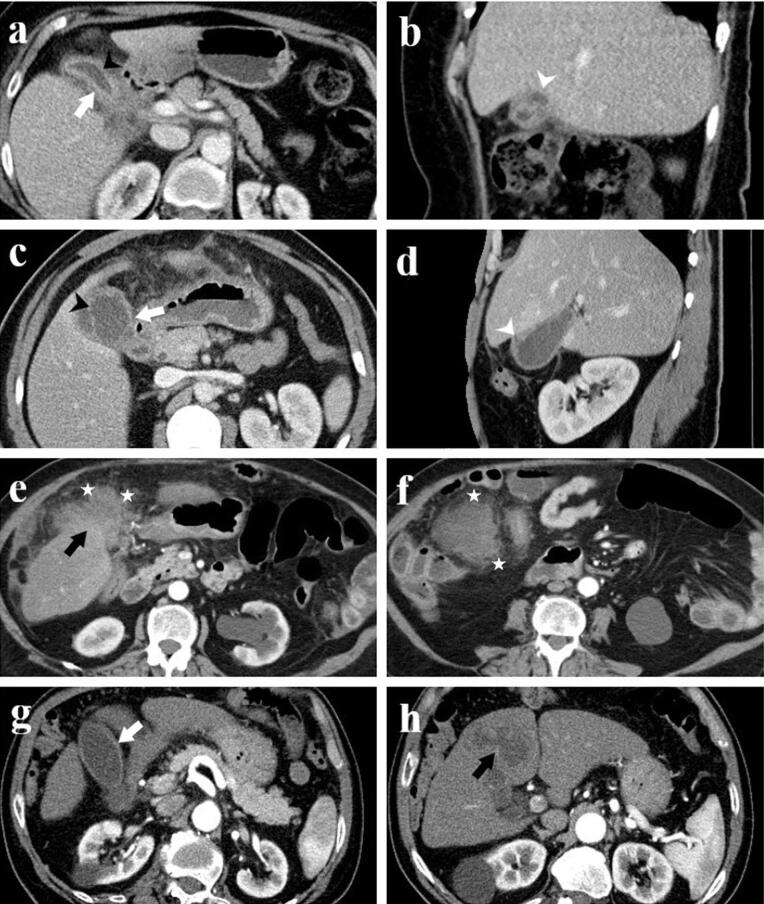

Background: Xanthogranulomatous cholecystitis (XGC) is a rare, chronic gallbladder inflammation often mistaken for gallbladder cancer (GBC) on imaging. Accurate differentiation is vital for appropriate treatment. This study aims to enhance computed tomography (CT) scan diagnostic accuracy for distinguishing XGC from GBC.

Methods: This retrospective study included patients diagnosed with XGC and GBC between 2014 and 2023. CT images of 70 patients (16 GBC, 54 XGC) were reviewed. Radiologists assessed CT parameters: gallbladder wall thickening, intramural hypoattenuating nodules, enhancement characteristics, mucosal line continuity, pericholecystic fat stranding, presence of stones, bile duct dilatation, hepatic invasion, invasion to adjacent structures, and lymph node size.

Results: Among 70 patients, there were 38 males (54%) and 32 females (46%), with a median age of 62 years. GBC patients were significantly older (median age 72 years) compared to XGC patients (60 years) (P=0.001). Diffuse gallbladder wall thickening was more frequent in XGC (70%) than GBC (12.5%) (P<0.001). Continuous mucosal lines and intramural hypoattenuating nodules were more common in XGC (P<0.001 and P=0.010, respectively). Intrahepatic bile duct dilatation and invasion to adjacent structures were significantly linked with GBC (P<0.001 and P=0.043). Lymph nodes with a short axis>8 mm indicated GBC (P<0.001), with a cutoff providing 71.4% sensitivity and 84% specificity (AUC: 0.843, P<0.001). CT showed 75% sensitivity (95% CI: 48-93%), 74% specificity (95% CI: 60%-85%), and 74% accuracy (95% CI: 62%-84%).

Conclusion: CT imaging can effectively differentiate XGC from GBC, and larger studies can further improve diagnostic accuracy.